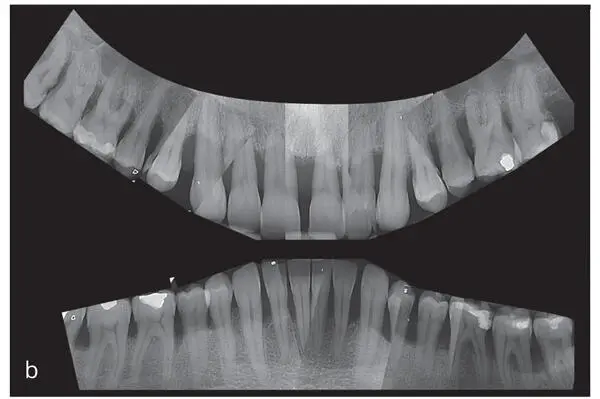

Figs 2-5a and bRadiographic examination of the patient introduced in Fig 2-3. (a) Panoramic radiograph and (b) intraoral radiographs. The radiographs show severe horizontal and vertical (locally) bone loss.